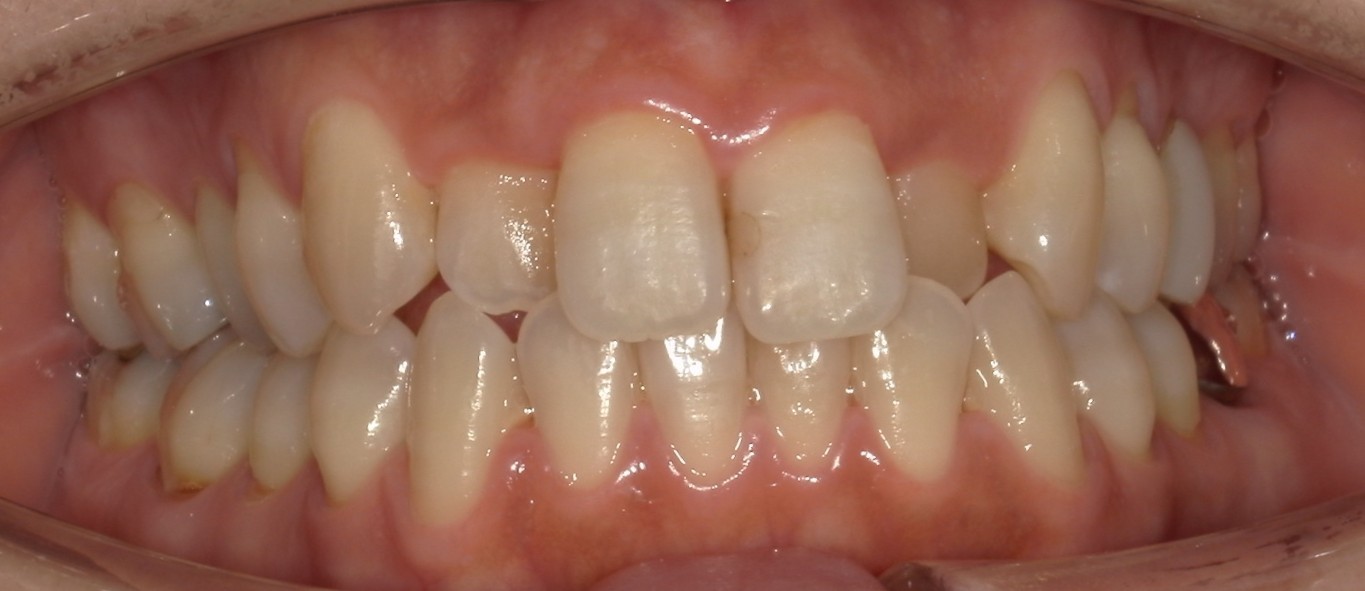

前歯だけの矯正の症例紹介①

Before

After

主訴

前歯の歯並びをキレイにしたい。

治療内容

ワイヤー矯正で治しました。

治療費

115,500円(税込)(リテーナー込み)

治療期間

2か月

通院回数

4回

想定されたリスク

※ブラックトライアングルができる可能性がありました。

多少ブラックトライアングルができたのでゴムを用いて閉鎖しました。比較的短期間で改善した症例です。